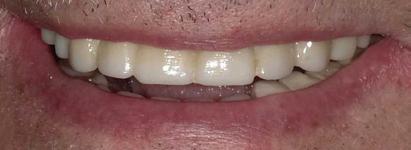

Can just four implants replace all of the teeth on the top or the bottom of your mouth? Thanks to advances in dental implant technology, that answer is a resounding yes.

Tooth loss is extremely common among adults, especially as we age. Rather than living with the discomfort and hassles of dentures, many people are opting for what is called “all-onfour” dental implant restoration.

An implant is a small titanium

screw that fits inside your jawbone and replaces the root-part of a missing tooth. Minor surgery is required to insert the implants. Once the implant is in place, a crown is attached to give you a highly realistic-looking and functional prosthetic tooth.

You do not need a dental implant for each and every one of your missing teeth. All you need is four precisely placed implants on the top of your mouth, and four on the bottom, to restore your full smile. That’s the beauty of the all-on-four. And because the implant is made of titanium, it has the unique ability to fuse to living bone and function as part of it. So eventually, the dental implant becomes part of the jawbone and serves as a strong, longlasting foundation for your new teeth.

Besides ensuring that your implants are permanently fixed in place, this bone fusion has another important benefit: it prevents future bone loss in the jaw. This helps to maintain a more youthful facial structure – and better

All-On-4 Dental Implants: A Reason To Smile Again

All-on-Four: One Full Arch Of Teeth, Four Dental Implants

To fully understand this remarkable technique for replacing teeth, you should first understand what a dental implant is. An implant is a small titanium screw that fits inside your jawbone and replaces the root-part of a missing tooth. Minor surgery is required to insert the implants. Once the implant is in place, a crown is attached to give you a highly realistic-looking and functional prosthetic tooth.

Here’s where it gets really interesting: You do not need a dental implant for each and every one of your missing teeth. All you need is four precisely placed implants on the top of your mouth, and four on the bottom, to restore your full smile. That’s the beauty of the all-on-four. And because the implant is made of titanium, it has the unique ability to fuse to living bone and function as part of it. So eventually, the dental implant becomes part of the jawbone and serves as a strong, long-lasting foundation for your new teeth.

Besides ensuring that your implants are permanently fixed in place, this bone fusion has another important benefit: it prevents future bone loss in the jaw. This helps to maintain a more youthful facial structure – and better oral health. But perhaps the biggest surprise about the all-on-four is how quickly it can transform your life.